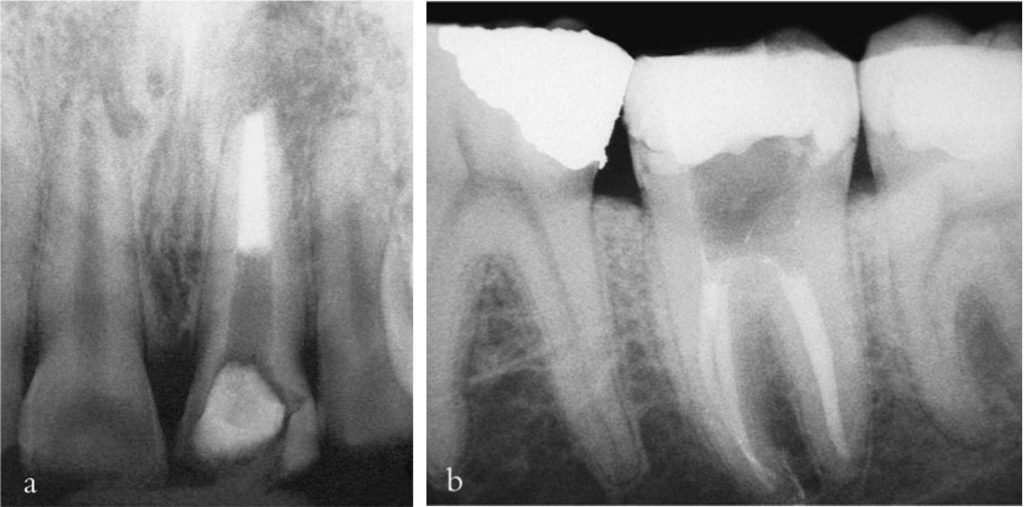

Trước hết cần đánh giá khả năng phục hồi răng, xét đến số lượng, chất lượng và vị trí mô thân răng còn lại, cũng như tình trạng nha chu.

Thăm dò cẩn thận quanh viền nướu bằng cây thăm dò nha chu giúp phát hiện các đặc điểm quan trọng như gãy dọc răng, có thể ảnh hưởng nghiêm trọng đến khả năng phục hồi và kế hoạch điều trị.

Thông thường, răng cần điều trị nội nha thường đã được phục hồi lớn trước đó hoặc bị bể vỡ và nhiễm khuẩn.

Cần loại bỏ mô sâu răng để ngăn ngừa rò rỉ và giảm nguy cơ mảnh ngà sâu chứa vi khuẩn đi vào ống tủy trong quá trình điều trị.

Lý tưởng nhất là nên có tối thiểu 2 mm mô răng lành nằm trên nướu bao quanh toàn bộ chu vi răng để thuận lợi cho phục hồi sau đó.

Nếu có bất kỳ nghi ngờ nào về khả năng phục hồi răng (xem chương 8) thì cần tháo bỏ hoàn toàn phục hồi hiện có để xác định rõ mức độ và vị trí mô răng lành còn lại.

Việc loại bỏ hoàn toàn phục hồi hiện tại được khuyến cáo trong nhiều trường hợp, vì có thể làm lộ ra các đường nứt ẩn không được phát hiện qua khám lâm sàng bên ngoài hay thăm dò nha chu.

Việc điều trị nội nha có thể khó khăn hơn nếu mở tủy xuyên qua mão, bởi vì các mốc giải phẫu răng bị che khuất bởi phục hình ngoài thân răng, dẫn đến khó xác định miệng ống tủy, loại bỏ nhầm quá nhiều mô răng lành hoặc thậm chí gây thủng.